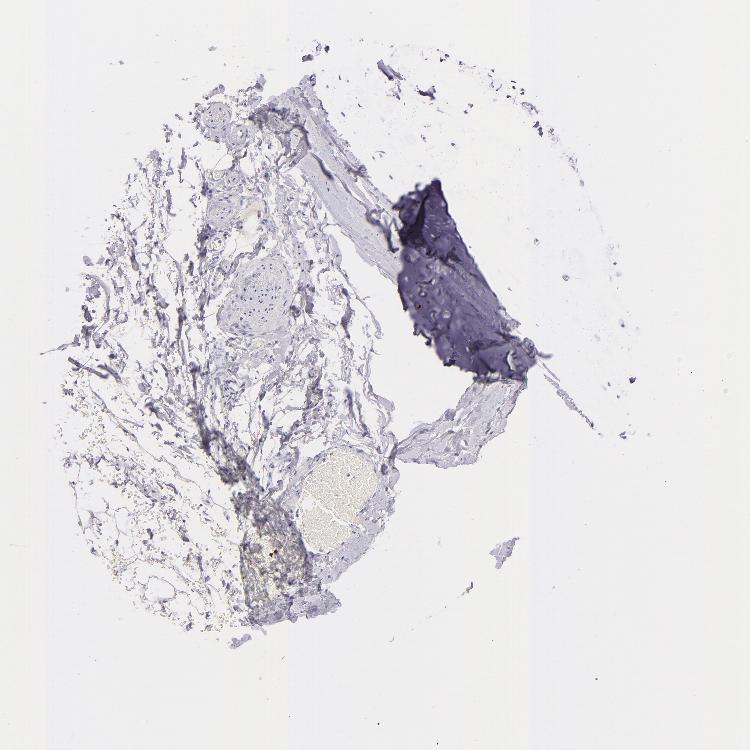

ADIPOSE TISSUE - Antibody stainingi

Antibody staining in the annotated cell types in the current human tissue is reported as not detected, low, medium, or high, based on conventional immunohistochemistry profiling in selected tissues. This score is based on the combination of the staining intensity and fraction of stained cells.

Each image is clickable and will lead to virtual microscopy that enables deeper exploration of all samples and also displays staining intensity scores, fraction scores and subcellular localization as well as patient and tissue information for each sample.

Antibody CAB002436

Adipocytes Not detected